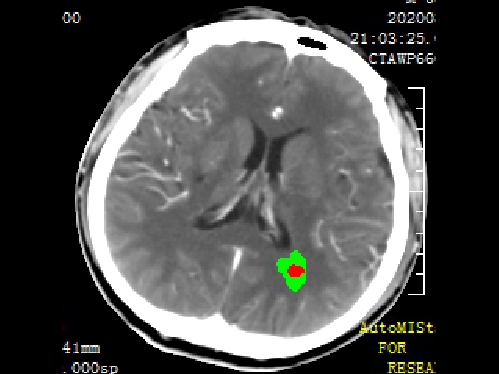

急诊予以静脉溶栓,同时完善头颈CTA+CTP、MIStar相关检查

结合CTA结果,提示左侧颈内动脉起始部至颈内动脉末端未见显影,起始部成鼠尾征改变,前交通动脉开放,双侧大脑中动脉显影良好。MIStar图像提示核心梗死灶和缺血半暗带较小,但是MTT提示左侧大脑中动脉流域区明显延长。